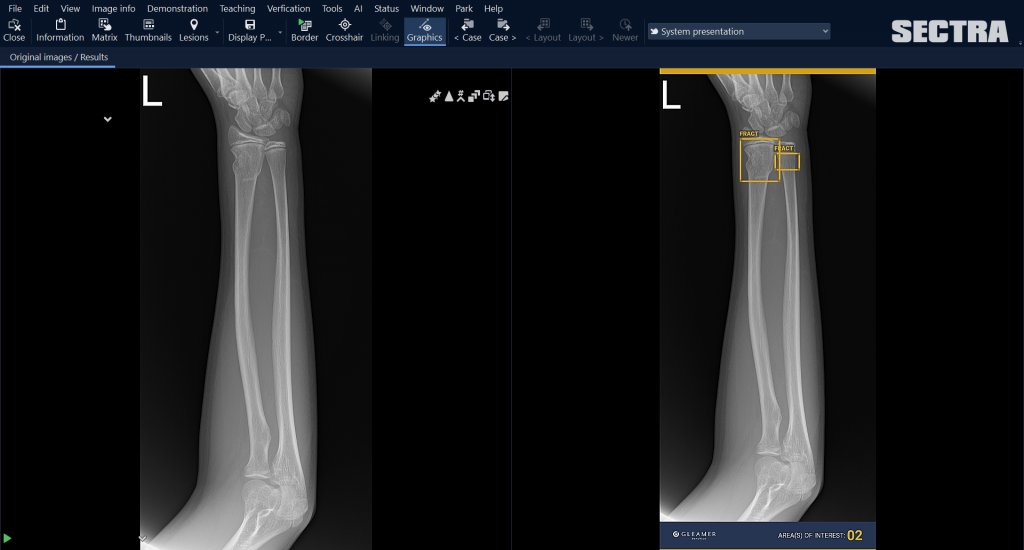

Sectra interviewde innovatiemanager Wilco Kleine en projectmanager ICT Julia Larsen van het Deventer Ziekenhuis. Het Deventer Ziekenhuis heeft de proof-of-concept fase doorlopen van de door Gleamer ontwikkelde applicatie BoneView, die radiologen ondersteunt bij het detecteren van botbreuken. Om de pilot gestructureerd en succesvol uit te voeren is gekozen voor de volgende fases: marktanalyse, retrospectieve studie voor lokale validatie, integratietest in schaduwmodus en de toepassing in de klinische praktijk. BoneView draait via de Sectra Amplifier Services en is geïntegreerd in het Sectra PACS.

Het Deventer Ziekenhuis wil AI inzetten voor verschillende doeleinden: het verminderen van de werkdruk en het verbeteren van de gezondheidsuitkomsten voor de patiënt. Deze logistieke inzet van AI “ondersteunt bij minder complexe beoordelingen met een acuut karakter.” Doel hiervan is om de acute zorg te optimaliseren, de werkdruk beter te verdelen én de snelheid voor de patiënt te verhogen. Met BoneView kan bijvoorbeeld de eerste detectie van botbreuken geautomatiseerd verlopen. Kleine: “Op die manier hoeft de medisch specialist niet ’s nachts mogelijke botbreuken te beoordelen wanneer er op de spoedeisende hulp (SEH) iemand binnenkomt. De AI kan de eerste beoordeling doen, die de radiologen de volgende ochtend dubbelchecken.”

Na de keuze om te starten met BoneView ging het Deventer Ziekenhuis de tool niet meteen in de praktijk gebruiken. In plaats daarvan was een retrospectieve studie aan de hand van lokale data een belangrijke stap om iedereen vertrouwen te geven in de resultaten. Deze studie gebruikte circa 500 onderzoeken uit het eigen PACS die de afgelopen jaren door een radioloog van het ziekenhuis zijn beoordeeld.

Kleine: “We hebben de beoordeling van het algoritme vergeleken met de beoordeling van de radioloog. Hoe verhouden die beoordelingen zich?” Het hieruit volgende betrouwbaarheidscijfer hangt af van de opbouw van de lokale patiëntpopulatie, beelden, röntgenapparatuur en beoordeling van de radiologen. Dit komt immers zelden precies overeen met de studie van de ontwikkelaars.

De evaluatie door de laboranten na afloop van de pilot liet zien dat zij vrijwel allemaal positief waren over de inzet van BoneView en het gebruik graag voortzetten. Zowel tijdens de dagdienst als in de avond- en nachtdienst hielp BoneView bij de beoordeling van het onderzoek, waardoor laboranten minder vaak de radioloog om een beoordeling vroegen. Dit levert voor de radioloog weer minder werkverstoringen op. De patiënt krijgt vaak sneller duidelijkheid en hoeft minder lang te wachten.